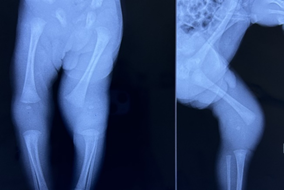

On the 3rd day of life, the neonate developed swelling of the left knee, including the lower thigh, along with restricted movement of the left leg, with the knee kept flexed and mildly tender. There were no signs of local inflammation or skin changes over the affected knee, and the local temperature over the swelling was not raised. A repeat CBC at 48 hours of age showed normal leukocyte counts, and CRP was non-reactive. Plain radiography of both knee joints revealed a wide joint space on the left side with the absent distal femoral epiphysis, contrary to the presence of the right femoral distal epiphysis visible due to the ossification of its center. However, despite the non-visualization of the distal femoral epiphysis on the left side, the femur and tibia/fibula on the affected side appeared to align normally (Figure 1); hence birth injury could not be suspected initially. The orthopedic surgeon suspected septic arthritis and aspirated a small amount of synovial fluid from the left knee joint. On evaluation, the fluid was clear, negative for pus cells, and the gram stain. The bacterial culture of synovial fluid was also negative after 24 hours of incubation.

Figure 1 Anteroposterior radiograph of both knee joints on day 3 of life showing a wide joint space on the left side with the absent distal femoral epiphysis.